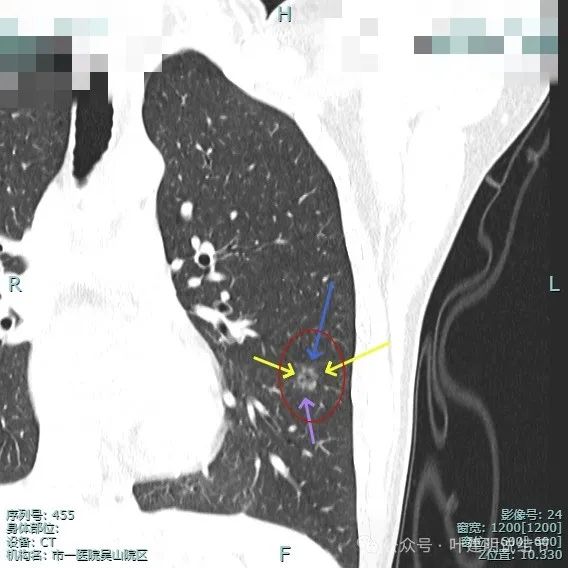

右侧病灶15:

病灶密度仍纯但不太均匀,整体轮廓与瘤肺边界清。

有小血管进入与类反晕征。

血管进入以及轮廓与边界清楚。

密度不均显杂乱。